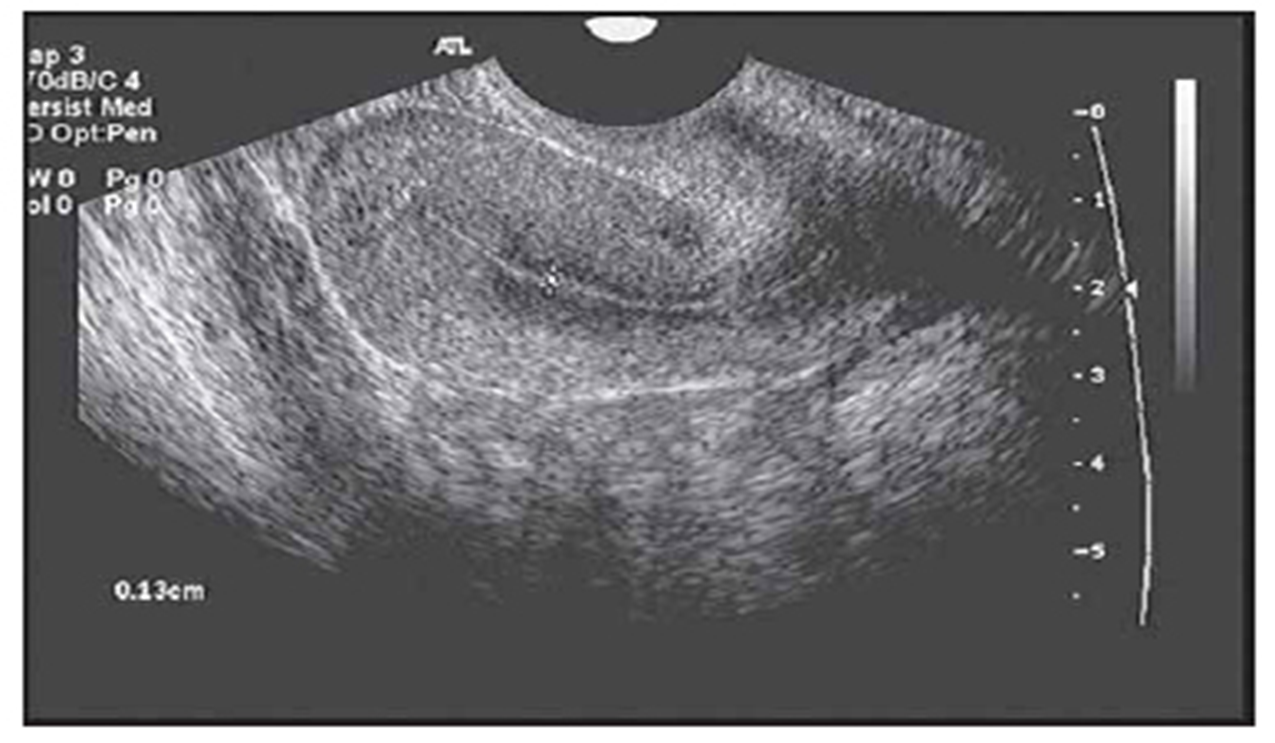

Post menopausal endometrium

postmenopausal

women

endometrial thickening more than 5 mm

is considered abnormal